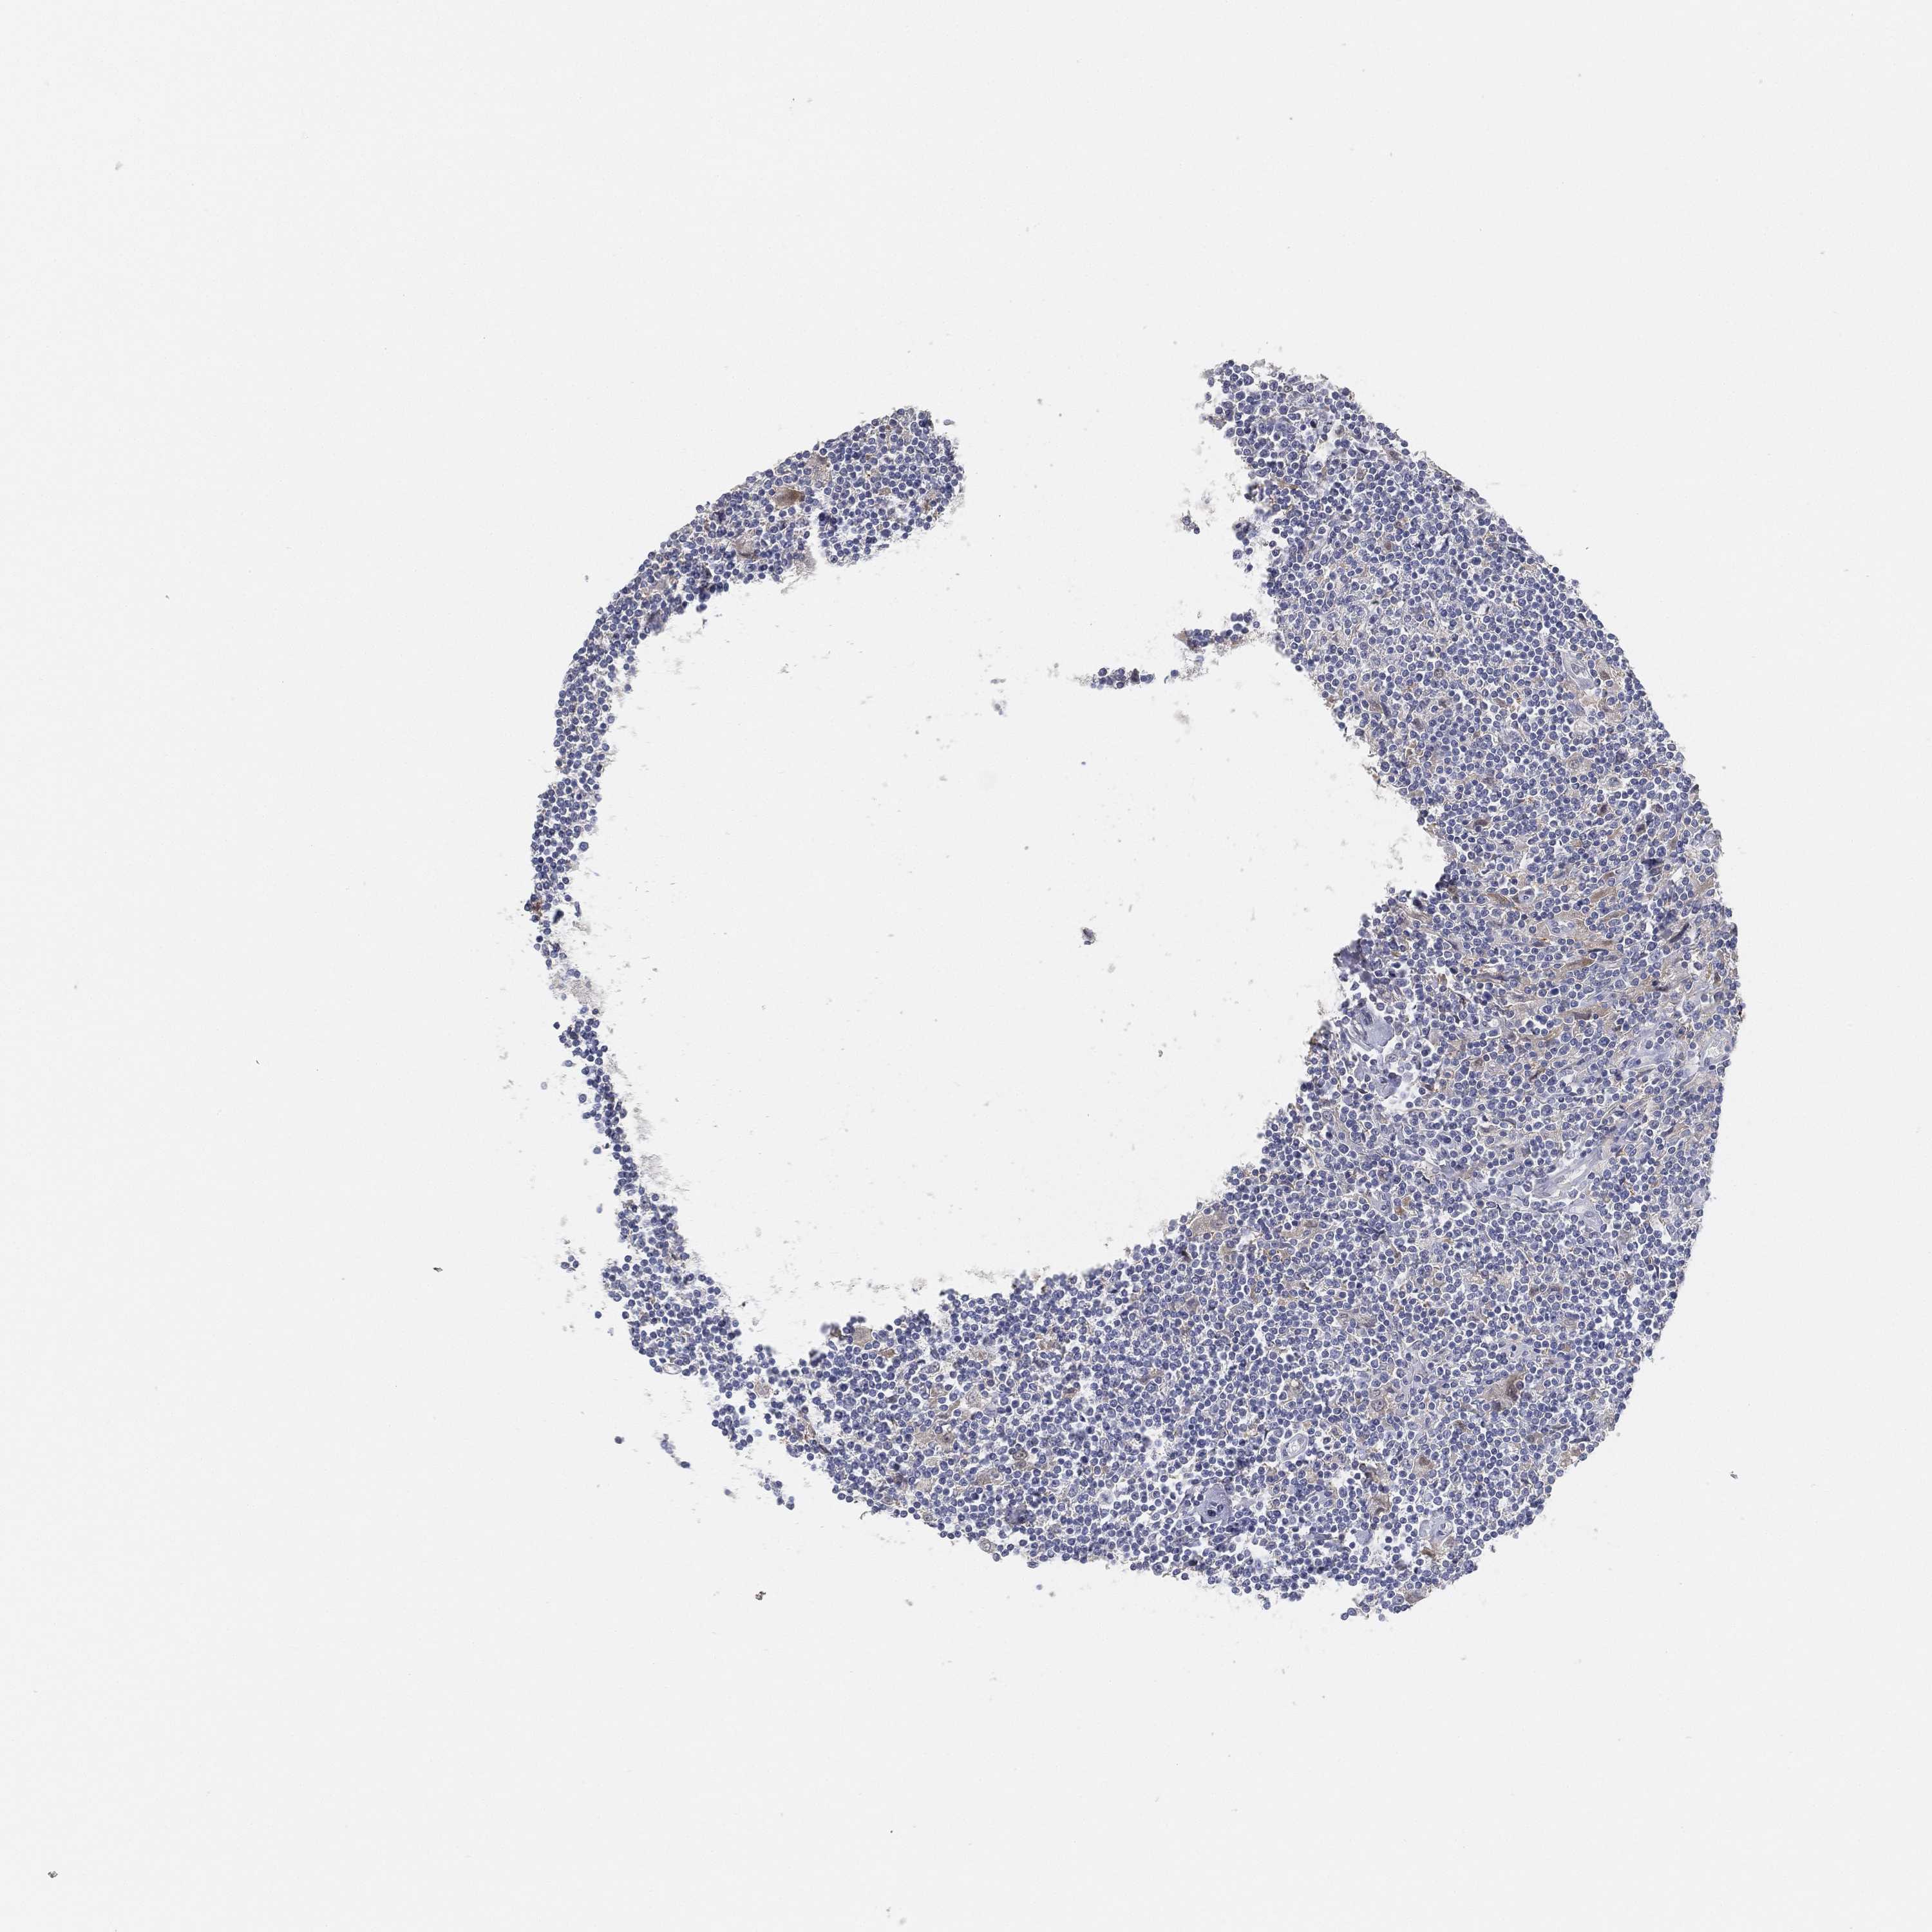

CANCER LYMPHOMA Show tissue menu

LYMPHOMA - Protein expressioni

A mouse-over function shows sample information and annotation data. Click on an image to view it in a full screen mode. Samples can be filtered based on level of antibody staining by selecting one or several of the following categories: high, medium, low and not detected. The assay and annotation is described here.

Each image is clickable and will lead to virtual microscopy that enables deeper exploration of all samples and also displays staining intensity scores, fraction scores and subcellular localization as well as patient and tissue information for each sample.

Antibody HPA026088

Malignant lymphoma, non-Hodgkin's type, Low grade

Malignant lymphoma, non-Hodgkin's type, High grade

Hodgkin's disease, NOS